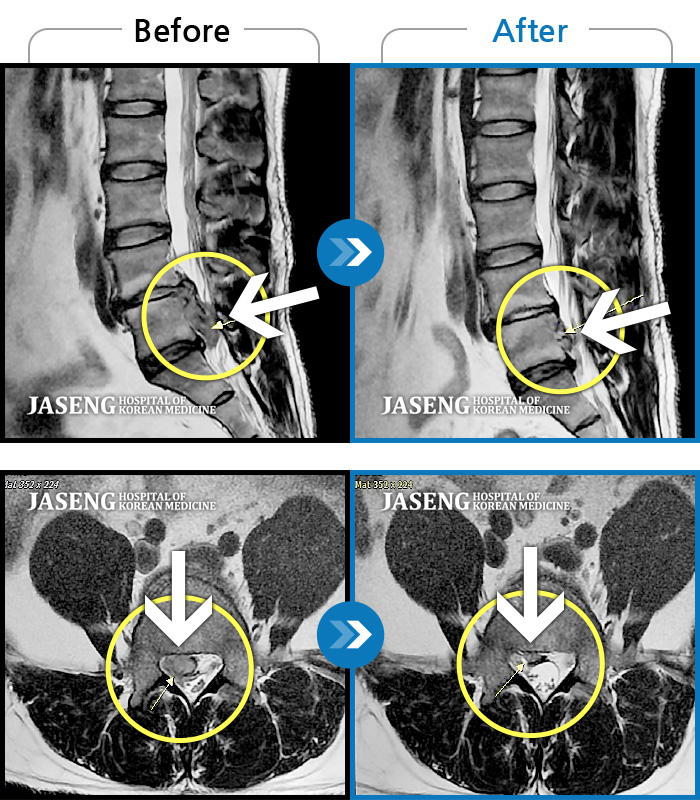

MRI 치료사례

양측 하요추부 통증과 우측 하지 후면부 통증